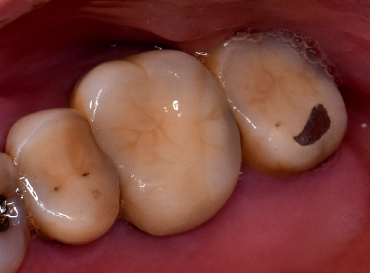

治用前の状態がこちらです

レントゲンを見ると、以前根っこの治療をしたところに膿がたまっているのがわかります。また、奥歯の被せ物も古くなり段差ができてあわなくなってきています。